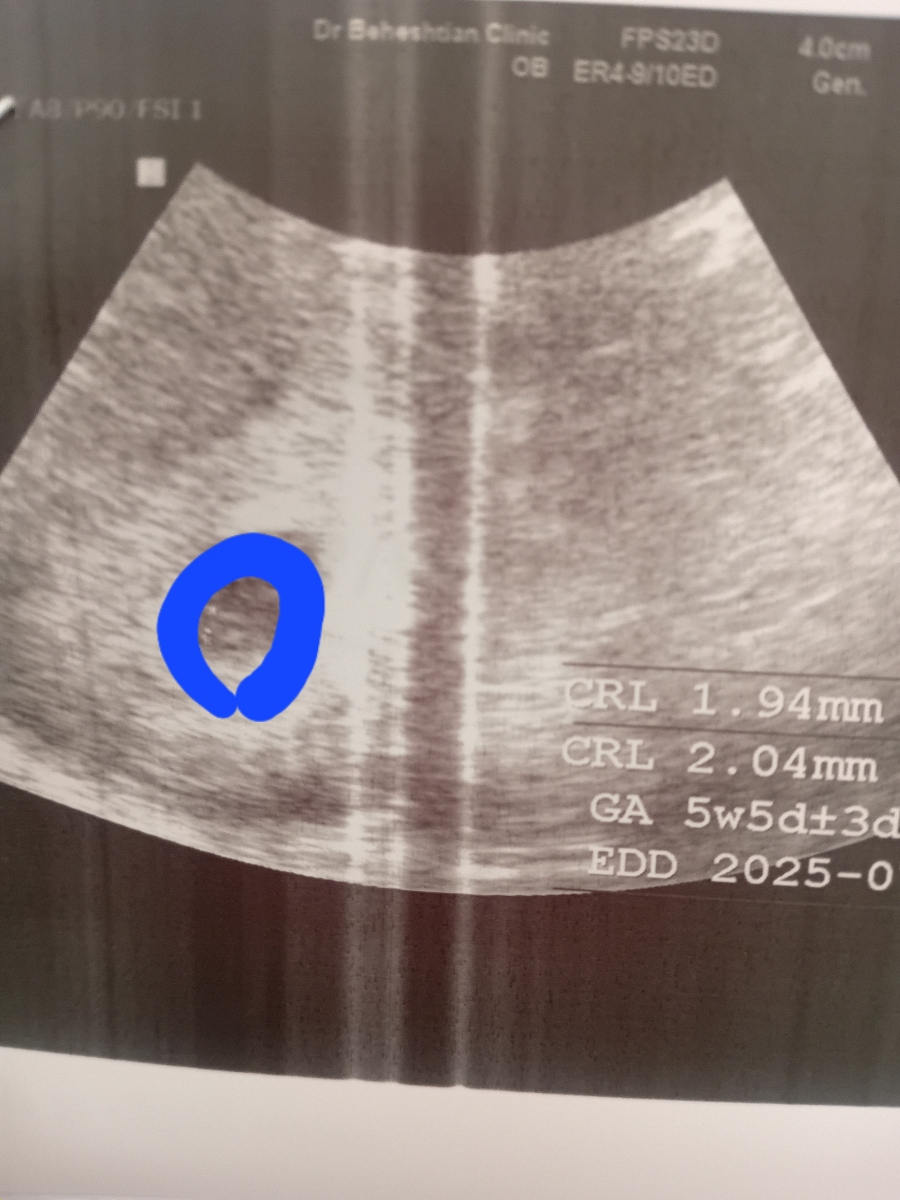

گف کیسه زرده هس فتال پلم هس فقط ضربانشو نمی تونم دقیق متوجه بشم ،شک دارم گف برا ضربان زوده ۵ هفته و ۵ روزی،حالا دیکه نمیدونم دقیقه یا ن

ن گف کیسه زرده و فتال پل هست

داخل برگه زد CRL مساوی۲ م م

اون چیز داخل ساک بارداری هم احتمال خیلی زیاد جنینه ولی چون دستگاه سونو کیفیت نداشته خوب توی عکس واضح نیست

اره عزیزم جنینه

ولی دستگاه سونو مطب دکترا ب اندازه دستگاه های سونوگرافی پیشرفته نیستن، واسه همین عکسا واضح نیست